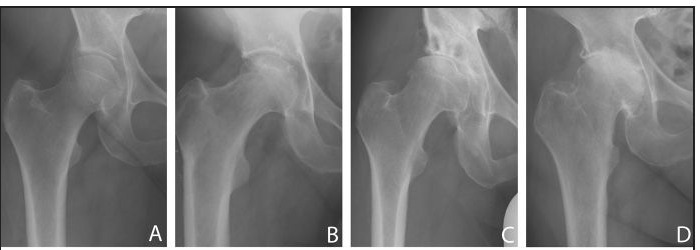

髋关节骨关节炎(OA)又称髋关节软骨病,是一种退行性疾病,其特点是髋臼关节软骨损伤导致生物力学逐渐改变。本研究的目的是确定2014年1月至2019年12月期间在Drobeta-Turnu Severin县急诊医院骨科和创伤科接受手术(髋关节置换术)的髋关节骨关节炎患者的发病率。此外,我们还建议收集所研究患者群体的发病率、年龄组分布、性别、生活条件和使用的关节成形术类型等详细信息。研究共纳入485名髋关节OA患者,主要诊断为老年患者,其中87.83%的患者年龄在60岁以上。在性别方面,该病主要影响女性,女性/男性比例为 2/1。

Osteoarthritis (OA) of the hip, also known as coxarthrosis, is a degenerative disease marked by gradual biomechanics alterations cause by articular cartilage damage in the coxofemural joint. The goal of this study was determining the incidence of patients with hip osteoarthritis who undergo surgery (hip arthroplasty) within the Department of Orthopedics and Traumatology of the Emergency County Hospital of Drobeta-Turnu Severin, hospitalized between January 2014 and December 2019. Furthermore, we proposed gathering details about incidence, distribution according to age group, gender, living conditions, and type of arthroplasty used in studied patient group. The study included 485 patients with hip OA mainly diagnosed in elderly patients, 87.83% being over 60 years old. In terms of gender, the disease primarily impacted women, with a female/male ratio of 2/1.